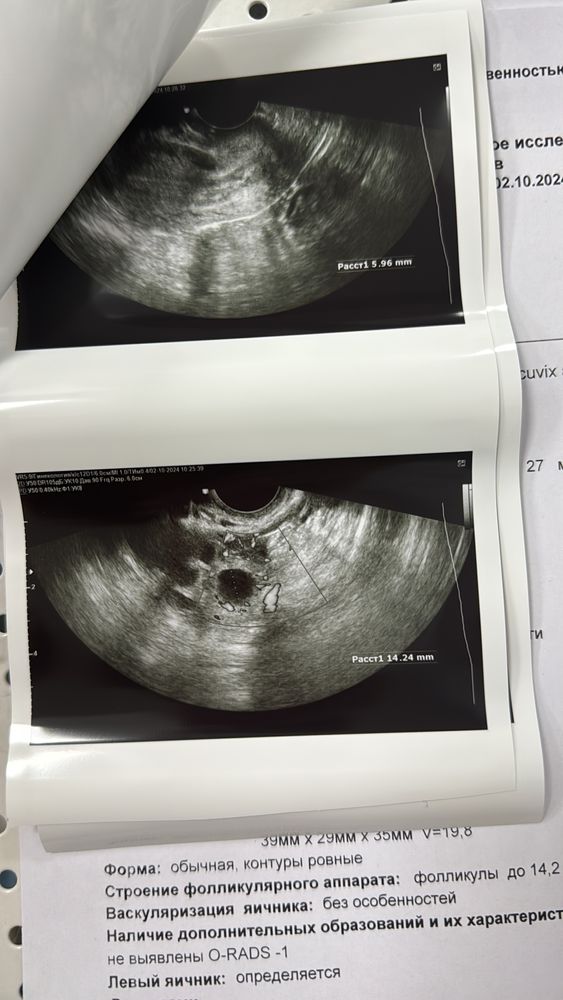

Ландыш Габдуллова в Зачатие год Узи Заключение УЗИ Проверьте пожалуйста, была ли овуляция 28 день цикла, месячные нерегулярные Посмотрите еще 20 записей на эту тему Отменить Ответить Нет ощущений На какое дпо делали УЗИ ? Чаты Беременных Выберите чат: Январята-2026 Февралята-2026 Мартята-2026 Апрелята-2026 Майчата-2026 Июнята-2026 Июлята-2026 Августята-2026